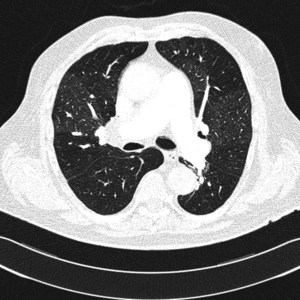

Zakrzepowo-zatorowe nadciśnienie płucne to nadciśnienie płucne spowodowane mechanicznym zamknięciem łożyska płucnego przez zorganizowane skrzepliny. Najczęściej jest to niekorzystne zejście epizodu ostrej zatorowości płucnej nazywane przewlekłą zatorowością płucną, a nie pierwotna in situ zakrzepica naczyń płucnych, chociaż w CTEPH klasyczne czynniki ryzyka żylnej choroby zakrzepowo-zatorowej występują rzadko [3]. Według definicji z aktualnych wytycznych Europejskiego Towarzystwa Kardiologicznego z 2009 r. CTEPH należy rozpoznawać przy współistnieniu przedwłośniczkowego nadciśnienia płucnego (średnie ciśnienie w tętnicy płucnej ≥25 mm Hg, ciśnienie zaklinowania w tętnicy płucnej ≤15 mm Hg, naczyniowy opór płucny >2 j. Wooda) i stwierdzeniu w badaniach obrazowych przewlekłych/zorganizowanych zawężających skrzeplin w sprężystych tętnicach płucnych [4]. Zwykle uważa się, że warunkiem rozpoznania CTEPH jest wykrycie przynajmniej jednego segmentalnego defektu perfuzji płucnej w scyntygrafii perfuzyjnej, tomografii komputerowej lub arteriografii tętnicy płucnej.

Klasyczne badanie radiologiczne klatki piersiowej nie rozstrzyga o rozpoznaniu, szczególnie we wczesnym okresie choroby. Wraz z postępem PH poszerza się jednak pień i główne gałęzie tętnic płucnych, a także obserwuje się cechy powiększenia prawej komory serca. Obecność obszarów beznaczyniowych w porównaniu z resztą pól płucnych może budzić podejrzenie CTEPH jako przyczyny PH.